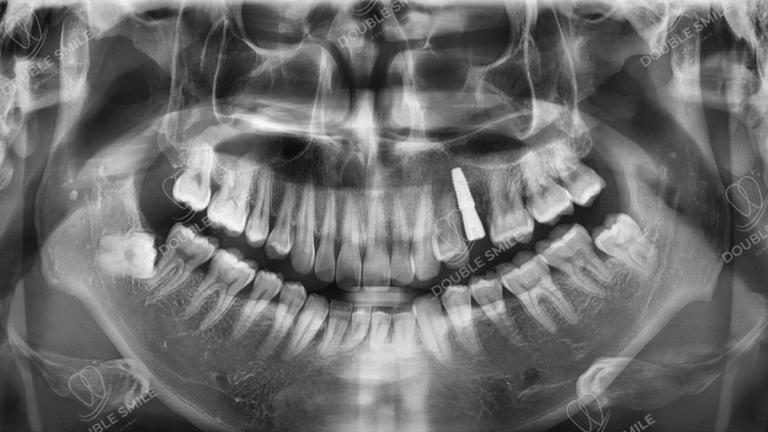

After